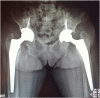

Simultaneous bilateral femoral neck fracture in a patient with renal osteodystrophy

We present a unique case of displaced simultaneous bilateral fractures, Garden 3 type, in a 49 year woman treated with non-cemented total hip arthroplasty. The patient showed a Harris hip score of 86 on the right hip and a 81 on the left side on the fourth postoperative year, besides a bilateral Trendelenburg gait, more pronounced on the right side. She needed a cane to walk, and felt pain in the left thigh. The X-ray showed a shortening of 0.9 cm and a left femoral varus. The other arthroplasty components showed good osseointegration and position. We found that the use of the uncemented total hip arthroplasty to treat a simultaneous bilateral fracture in renal osteodystrophy patients has satisfactory results at a four year follow-up. According to the OCEBM Levels of Evidence Working Group, this study is graded as a Level of Evidence IV.